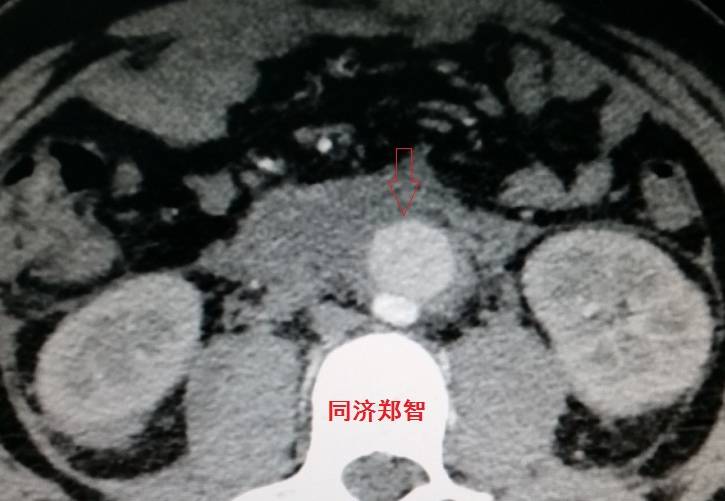

病例四

腹部平扫CT提示腹主动脉增宽,CTA证实为腹主动脉局限性夹层(红箭头所示)